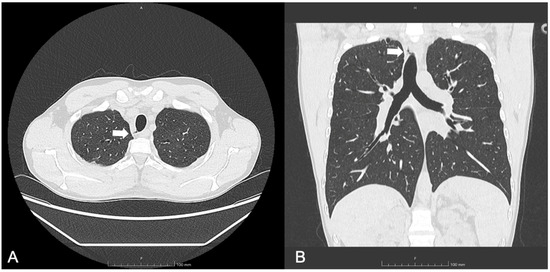

3.3. Patient 3

| 10, F | F508del/ F508del | SA, first PA detection | 117 | 16 | 1, 9, right posterolateral at T1 level | No | Visible radiologically, not endoscopically | Not yet performed |